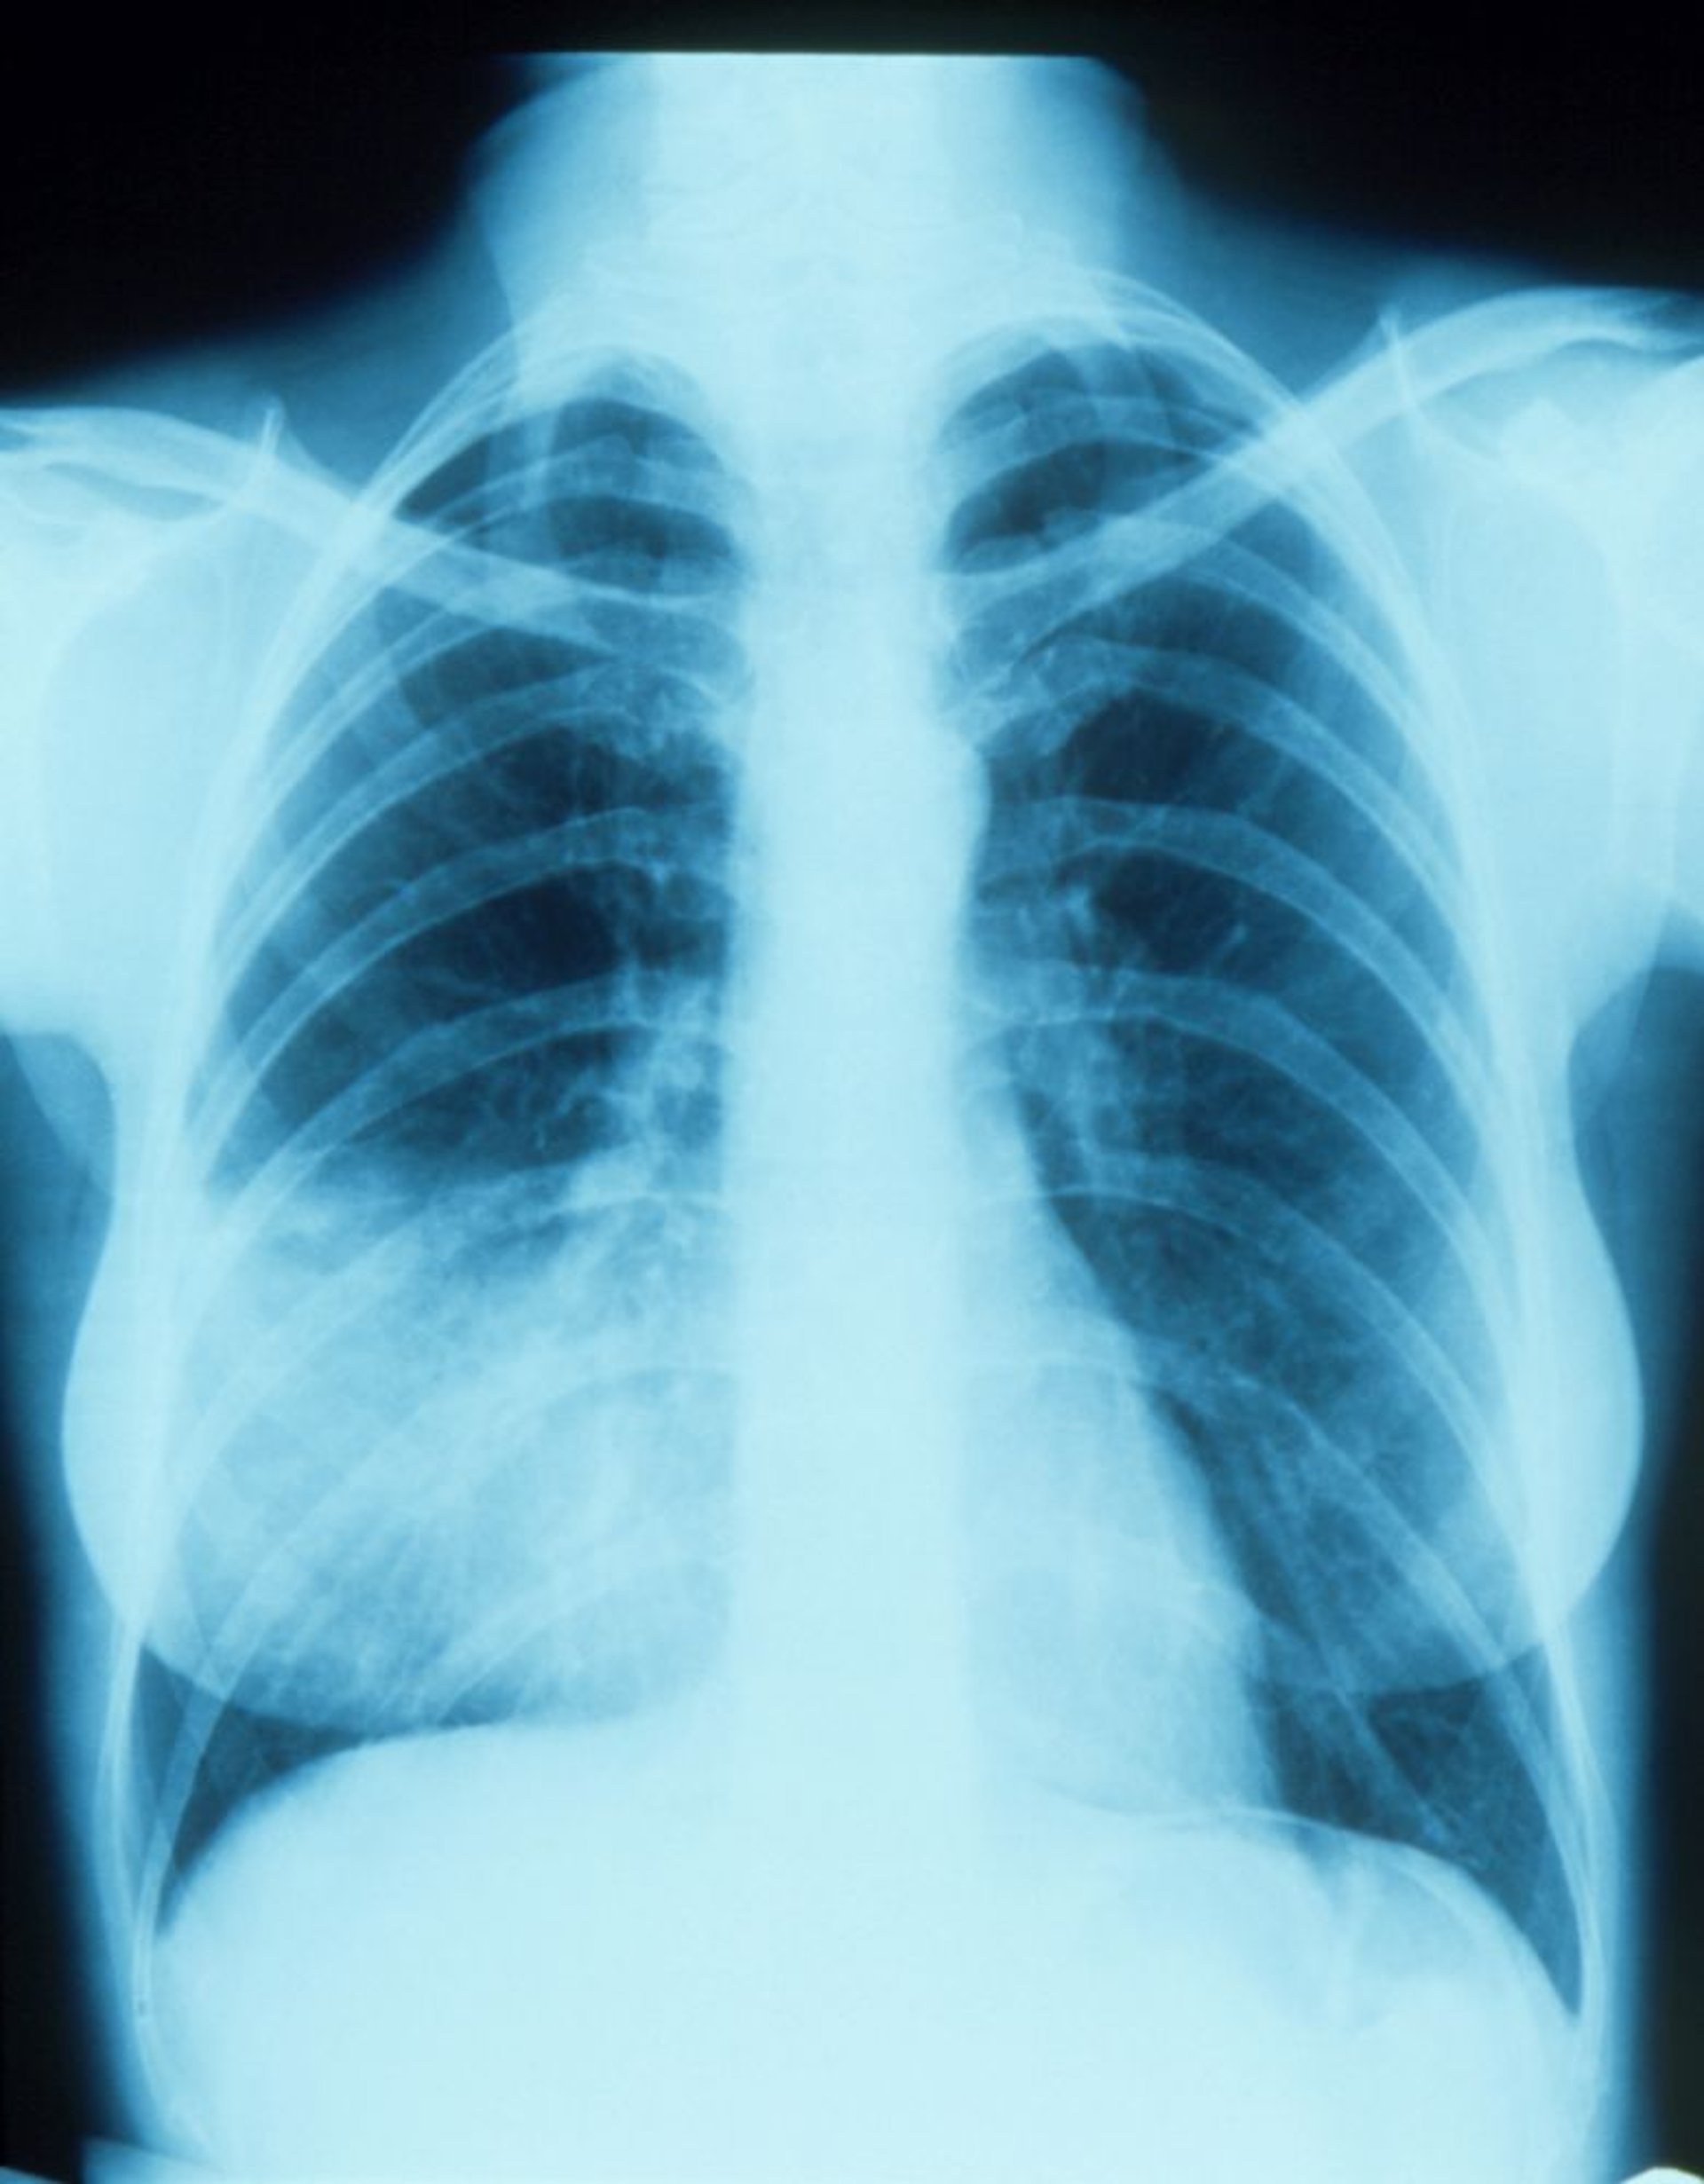

シルエットサインを伴う右中葉の肺炎

この胸部X線画像では,右心縁と融合するような浸潤影(シルエットサイン)がみられる。シルエットサインは,放射線透過性が同等の2つの構造物が連続した位置にあることを示す;右心縁と連続している肺の領域は右中葉であるため,右中葉に肺炎の浸潤影が存在することがわかる。